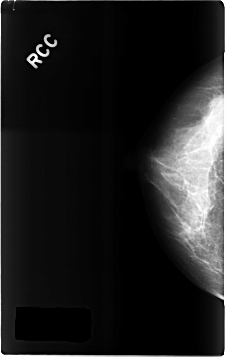

C_0300_1.RIGHT_CC

RIGHT_CC LINES 4632 PIXELS_PER_LINE 2928 BITS_PER_PIXEL 12 RESOLUTION 50 NON_OVERLAY